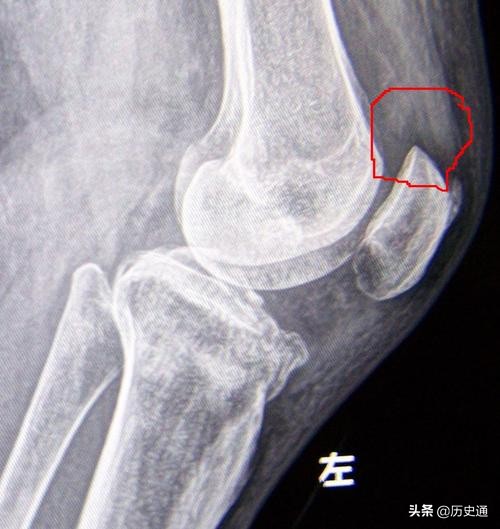

当时,西医的骨科治疗手法也在北京传开。尤其东交民巷的一家德国医院的骨科影响很大。这样中国传统的正骨手法与西医的骨科治疗手法就碰撞在了一起,无形之中不可避免将有一场切磋与较量。那件事,我记得很清楚。有一个人髌骨骨折了,住到了这家东交民巷的德国医院。然而,由于整个断了,病人疼得厉害,德国医院给他打了石膏,但还是固定不住,最后医院也实在没有办法了。即使这样,家属请我师父和我去看看,但人家医院还是不让去看。医院认为,自己的骨科技术很高都治不好这位病人,更不用说一位民间的正骨师父。

最后,禁不住家属的请求,我师父就以看朋友的名义去了这家医院。我师父看到这位病人后,感觉医院给病人治疗的不太合适。于是,师父建议上小夹板。因为,中医治疗需要箍上,打上夹板,治疗髌骨骨折,打上小夹板,有弹性,可调节松紧度,系的带,打的扣,不会压到皮肤。打上小夹板,病人可以动静结合,适度调节,毕竟光动也不行,老不动也不行。而西医打上石膏,经常三个月不动,他们认为必须接平,不接平就会形成创伤关节炎。我那时就留心了这点。于是,我去各个骨科查找这样的病例,最后找了七个。其中三个是骨质愈合,四个有粉碎的,纤维愈合,不平。然而,几年后进行观察,七个病例中没有一人发生创伤性关节炎,并且这些人都是出大力的人,装卸工人或者拉排子车的劳动者。不得不说,在这次较量与切磋中,我师父技高一筹,治愈了那位髌骨骨折,疼痛不堪的病人。

髌骨骨折